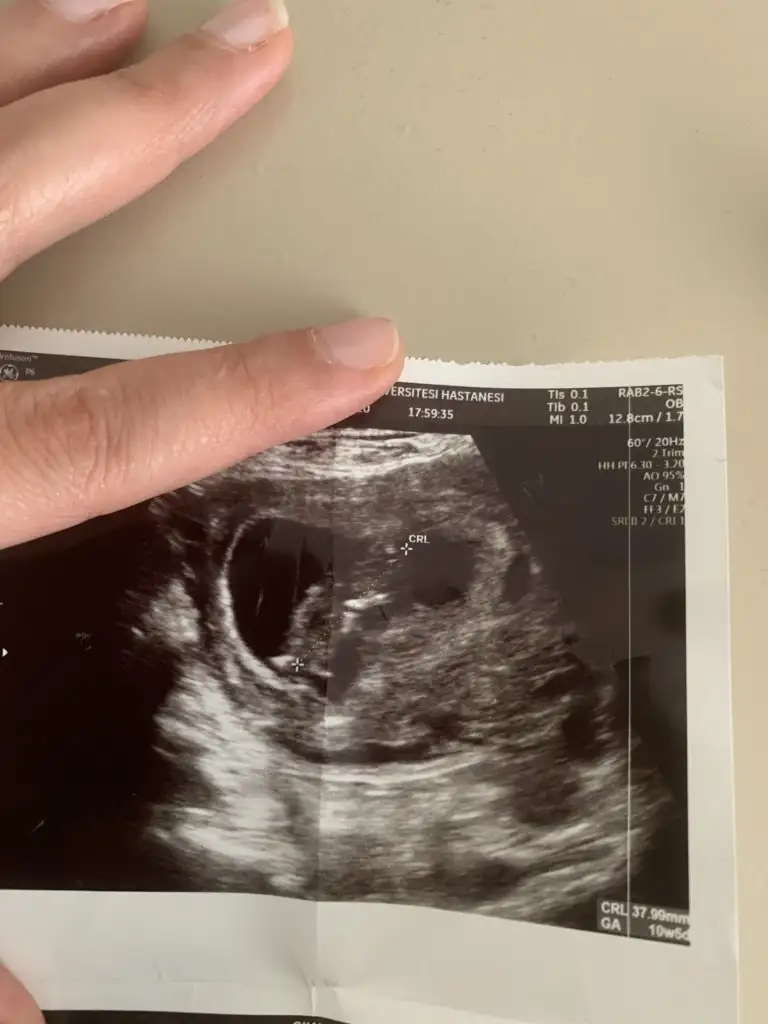

IMG-20200215-WA0001.webp

10+2yiz ama burda daha dr kontrolumüze var ben çıkıntı falan göremedim kızlar ya yardim edin 😅